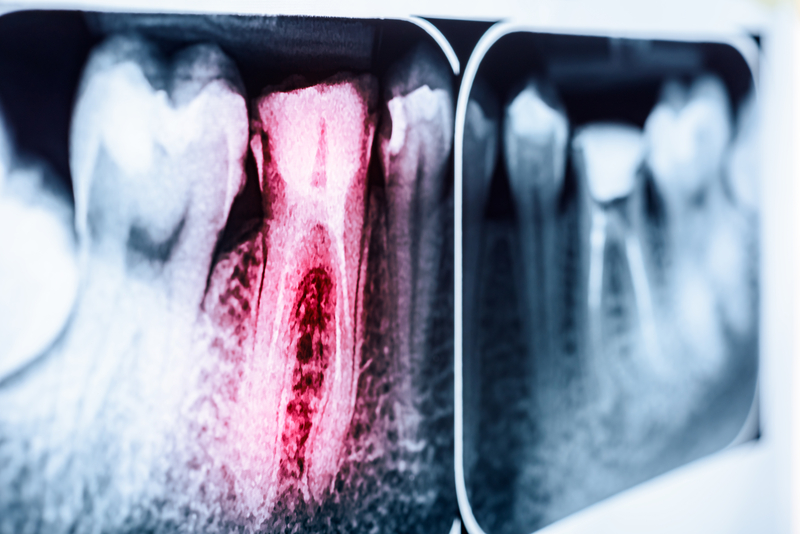

蛀牙不只影響口腔健康狀況,許多研究都證實,牙齒疾病與系統性疾病有密切的相關性,更與許多心血管重大疾病息息相關。

國泰綜合醫院口腔醫學科主任楊岳炤指出,牙齒疾病與系統性疾病密切相關根據美國心臟病學會研究發現,口腔清潔不佳容易發生蛀牙,而導致蛀牙相關細菌,同時會隨著血液循環系統影響全身,造成心血管內膜發炎、心血管硬化狹窄,大幅提升罹患心血管疾病的風險,例如:動脈粥狀硬化、心肌炎、心肌梗塞等發病

率,都會大幅增加2倍以上。

嚴重蛀牙,導致大量細菌進入血液臨床上,有個案因為嚴重蛀牙,導致大量細菌進入血液,發展成一定程度的菌血症狀態,進而感染心臟瓣膜或心臟內膜,造成感染性心內膜炎,這種疾病在心血管疾病中有很高的致命風險。

楊岳炤說明,當口腔中的蛀牙細菌侵入牙齦組織傷口,就會隨著血液循環系統影響全身,若是細菌流經心臟血管,將沉積於心血管內膜、增加刺激炎性因子,造成心血管內膜發炎、管徑變得狹窄,可能會提高發生心肌炎、心肌梗塞的風險。